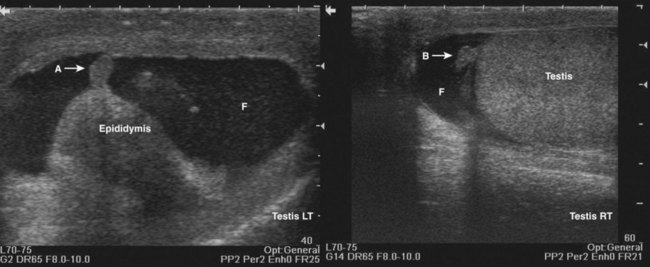

Some patients are not favorable candidates for renal ultrasonography. Obesity, intestinal gas, and physical deformity may be impediments to complete renal evaluation. Renal ultrasonography has poor sensitivity for renal masses less than 2 cm (Warshauer et al, 1988). There is a lack of specificity for renal tumor type except for angiomyolipoma. Angiomyolipoma has characteristics that are distinctive on ultrasonography (highly echoic), but some small renal cell carcinomas have been shown to be indistinguishable from angiomyolipoma by ultrasound criteria (Yamashita et al, 1992; Forman et al, 1993).

Transabdominal pelvic ultrasonography is a tremendously versatile tool for the urologist. It is a noninvasive method for evaluating the lower urinary tract and prostate in men and the bladder in women. A curved array transducer of 3.5 to 5 MHz is most commonly employed to perform transabdominal ultrasonography. In pediatric patients a higher-frequency transducer may be used. In cases where only a residual urine or bladder volume is to be determined, an automated bladder scanner is often employed.

Bladder ultrasonography is most commonly performed with the patient supine and the sonographer on the patient’s right side. The scan should be performed in a warm room, and the patient draped to provide for comfort and privacy. If necessary, a roll may be placed beneath the patient’s hips. Scanning technique depends on the circumstances and the reason for the examination but in general should be performed with a moderately filled bladder. The bladder should be scanned in a sagittal and transverse manner angling the probe into the pelvis so that the bladder can be visualized beneath the pubic bone. Although the prostate cannot be imaged with the same resolution achieved during transrectal scanning, the size and morphology of the prostate can be demonstrated. Although transabdominal scanning is the most common means of evaluating the bladder, the bladder may also be assessed via a transvaginal and transrectal approach. These approaches are useful in patients who are obese or who are not suitable candidates for transabdominal scanning.

Transabdominal pelvic ultrasonography should include evaluation of the lumen of the bladder, as well as bladder wall configuration and thickness. The presence of specific lesions such as stones or tumors should be documented. The structures immediately surrounding the bladder may also be evaluated including the distal ureters, the prostate in men, and the uterus and ovaries in women (Fig. 4–34). The emergence of urine from the ureteral orifices (ureteral jets) can be demonstrated. The clinical value of demonstrating ureteral jets has been questioned. Up to 10 minutes of continuous observation may be required to verify the absence of a ureteral jet (Fig. 4–35) (Delair and Kurzrock, 2006).